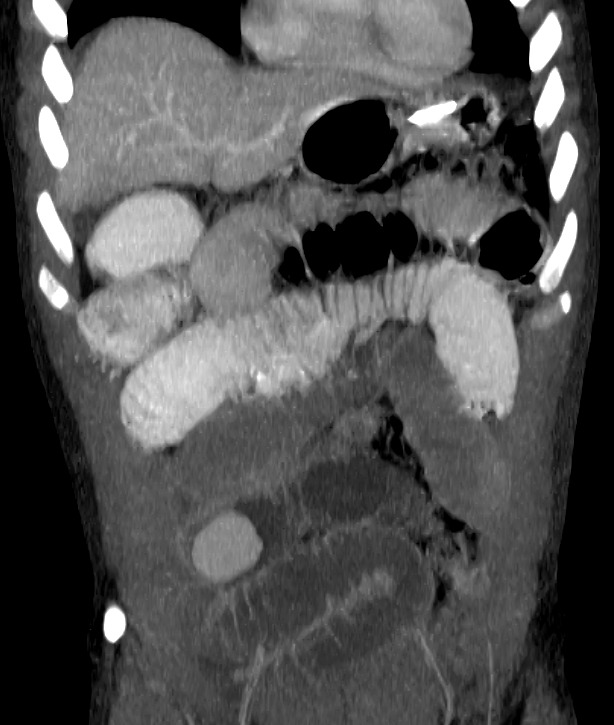

Lipoma intestinal: frecuente como punto guía o cabeza de invaginación en el instestino delgado. Aquí presentamos un caso de lipoma intraluminal en el colon, que producia obstrucción y cambios inflamatorios en el colon ascendente.